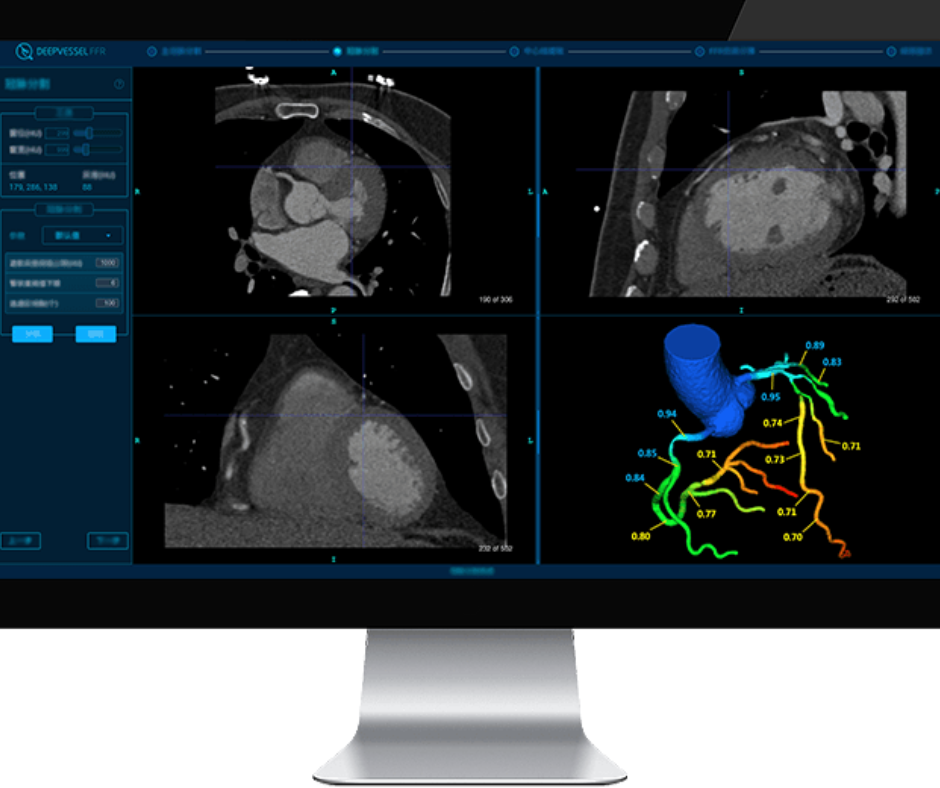

Employing deep learning capabilities, the DeepVessel FFR reportedly provides enhanced non-invasive evaluation of coronary arteries through semi-automated analysis of coronary computed tomography angiography (CCTA) imaging.